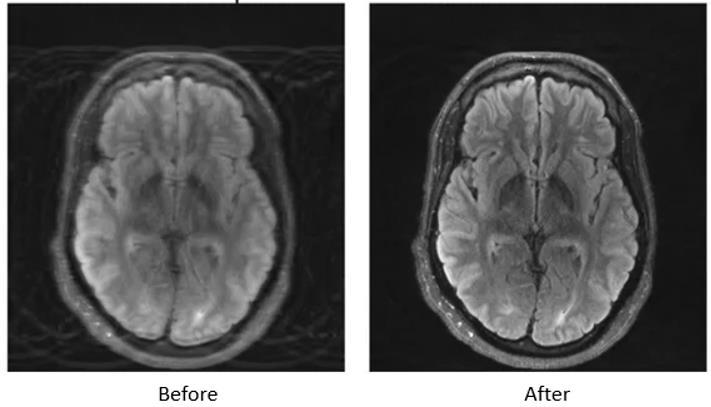

ConvolutionalNeuralNetworksarecentralinMRIimageenhancement,especiallyregardingimageresolutionandquality. In MRI scanning, resolution is often hampered because of time constraints and discomfort to the subject, causing poor image quality. CNNs solve the problem of image resolution through super-resolution techniques that upscale lowresolution images to high-resolution ones. The models learn, using multiple layers of convolutional filters, to extract minuteanatomical detail cortical foldsandsubtletissue boundaries thatmightnot be readilyapparentinlow-resolution scans. This ability is particularly important in neuroimaging, where accuracy regarding structural details is crucial in mappingbrainregionsorin detectingmicrostructural abnormalities.The bestpossibleresolutionupscaleofMRIimages byCNNs-afeaturethatprovidesradiologistswithimprovedimageswillbeanadditiontothefightagainstapatientlosing anopportunityforearlydetectionofhis/hermedicalcondition.

Another critical challenge that faces MRI imaging is noise, which can obscure some details and complicate the whole thing'sinterpretation.However,CNNsexcelindenoisingthoseMRIscansbyfirstidentifyingadifferencebetweenrandom noise and actual tissue characteristics. They are trained on datasets with paired images: one clean image, andone noisy image-pair for this technique to work well by successfully removing unwanted noise while keeping the relevant anatomical features. For example, with low-field MRIs, wherein signals are weak, CNNs can increase clarity significantly and enable a better analysis of structures such as white matter in the brain.The denoising process is needed in treating processes like multiple sclerosis and stroke because clear visualization of lesions is not only advantageous but also necessaryfortreatment.

In addition, CNNs are used for motion artifact correction, which is a common issue with MRI scans caused by the movement of a patient. While undergoing an MRI scan, any movement of the patient can result in blurring or ghosting artifacts that compromise image quality. With this, CNNs try to learn a set of data that includes artifacts-affected images withcorrectedversionsfromwhichtheycanconstructacleaneroutput.Thisapplicationisparticularlyadvantageouswith pediatric imaging because cooperation from the child during the imaging process can be limited and reducing repeated scanswouldbehighonthelistofpriorities.

Generative Adversarial Networks (GAN) come in next to provide another wave of sophistication to MRI imaging due to theirpeculiarroleinimagesynthesisandcontrastenhancement.Contrastisoftenkeyindistinguishingvarioussofttissues in MRI imaging. Unlike CNNs, which mostly boost visibility in already existing images, GANs take things even one step further, with the potential to generate entirely new high-quality images out of noisy or incomplete data. The generator networkgeneratessyntheticimages,whilethediscriminatornetworkprovidesjudgmentsonthoseimagesandscoldsthe generator to come up with amore realistic output. This adversarial arrangement works particularly well in completing missingdetailsonMRIscansthatsufferfromincompletedatabecauseofrapidscanningprotocolsorlimitedfieldofview. Thesyntheticdata generatedby a GAN alsoservesto enhance the variability inAI model training when confronted with varyingimageconditions.

Also, GANs come out as extremely powerful contrast enhancers. In MRI imaging, contrast is of the essence for differentiatingamongdifferentkindsofsofttissues.GANscanbetrainedtomaximizecontrastenhancementoutofimages with different qualities of contrast, thus counteracting it: structures of critical importance are therefore brought into sharper view. This can help detect soft tissue structures in the brain or the liver, for instance, where one should differentiatebetweennormalandpathologicalareas.Foroneexample,tinylesionsorsubliminalvascularstructuresmay beviewedmorebrightlyandeasily,thuspermittinggreaterdiagnosticconfidenceandchanceforearlydiseasedetection.

Figure 4: MRI scan comparison showing before and after AI enhancement, highlighting noise reduction, motion artifact correction, and improved resolution.